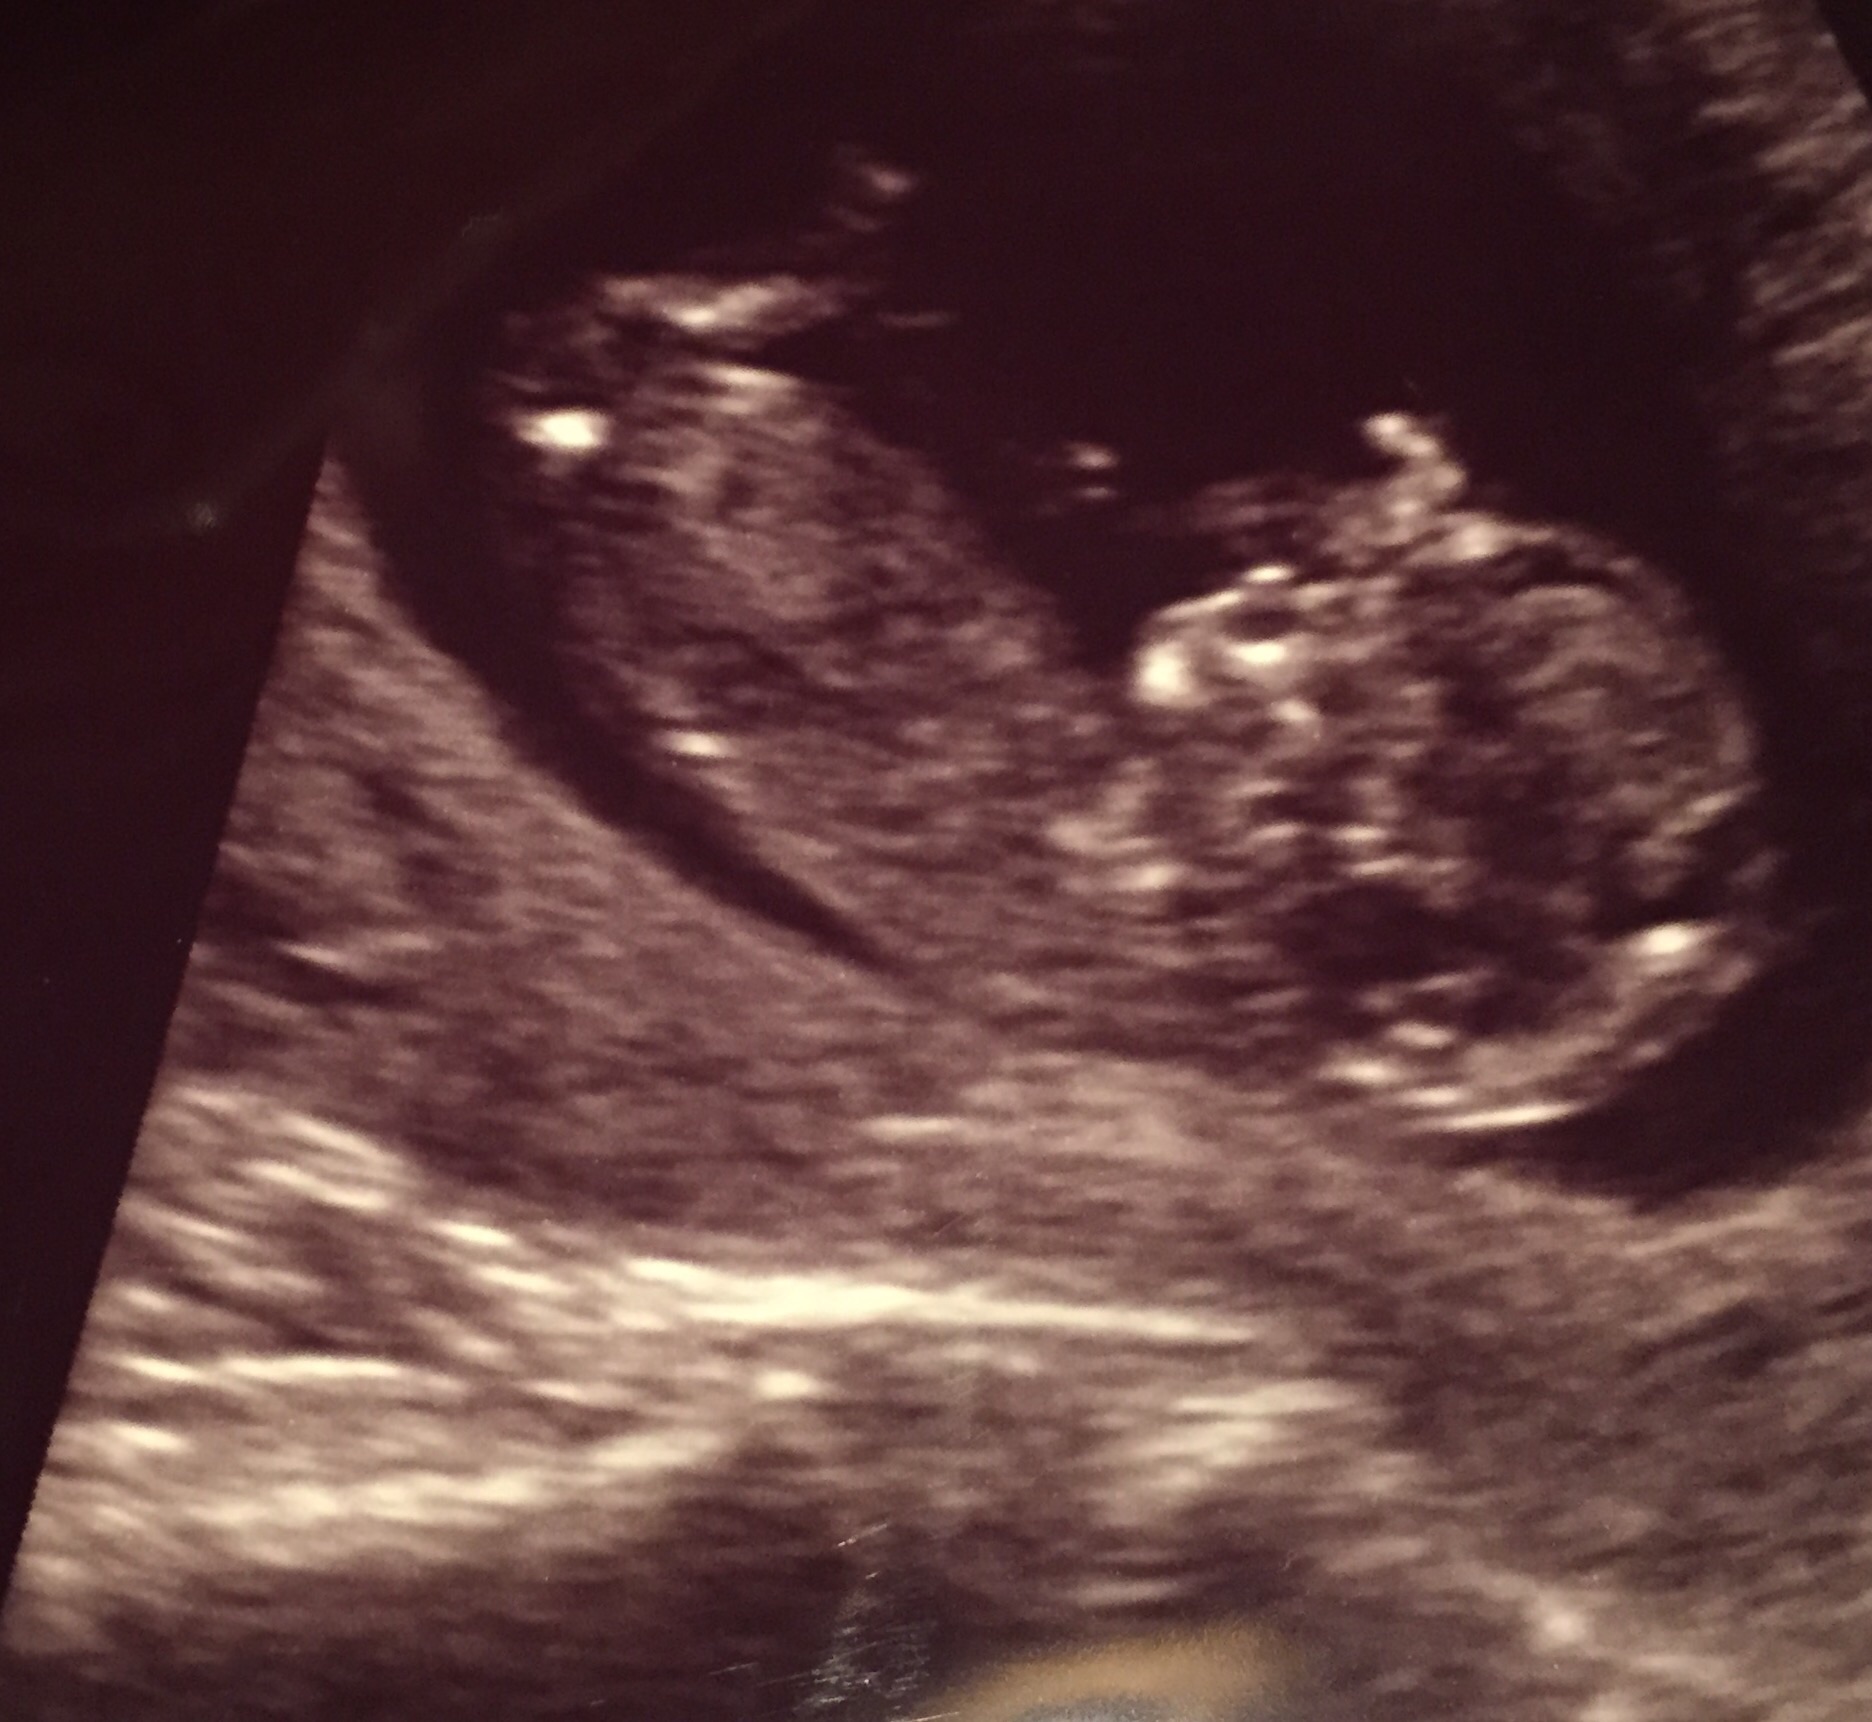

Had our first ultrasound yesterday! Found out I'm 11w2d which means I'm teetering between November/December. My due date as it stands is November 24th so right around thanksgiving It was just so surreal seeing the baby there with my DH. We were both just so happy to see a little baby there... it waved its arms a bit which was just so adorable.

Didn't catch what the heartrate was, but we definitely saw its little heart flickering Just so freaking amazing